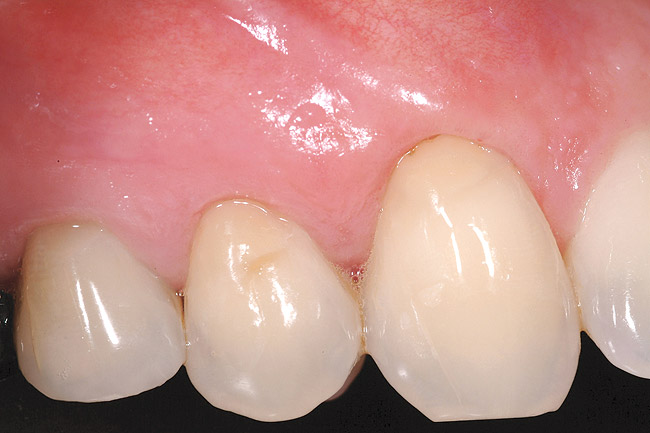

A 54-year-old non-smoking woman presented for correction of deep-wide gingival recession in the maxillary anterior (Figure 1 through Figure 3). The patient’s desires were to correct the gingival recession, balance the heights of contour of the tissues, and possibly undergo esthetic enhancement of the maxillary anterior with veneer restorations.

Figure 1  Case One Pretreatment clinical view, Case 1, maxillary right.

Figure 1

Figure 2  Case One Pretreatment clinical view, Case 1, maxillary anterior.

Figure 2

Figure 3  Case One Pretreatment clinical view, Case 1, maxillary left.

Figure 3